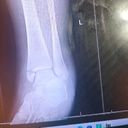

Hi my name is Shelisa and am fundraising towards a minor foot surgery this is important to me because if i don't perform this surgery i will be permanently disabled. I prayed everyday for help to perform my operation and hope it comes through successfully. Thank you